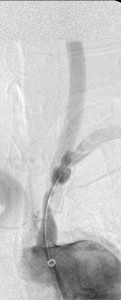

The 4 images you see above were recorded by me during primary stenting of irregular atherosclerotic stenosis of the left subclavian artery in a 54-year-old Hispanic female who was referred to my interventional radiology clinic for management of the stenosis. She had presented to her primary care physician with symptoms of hindbrain ischemia upon using her left upper limb and earlier workup confirmed left subclavian arterial stenosis. The 2 top images illustrate the character and severity of her disease, the first image in the bottom row shows the process of balloon-expandable stenting of the disease, while the 2nd image in the bottom row reveals complete elimination of the stenosis and reappearance of the left vertebral and internal mammary arteries, which were invisible on the pre-intervention angiograms reflecting the severity of the stenosis.